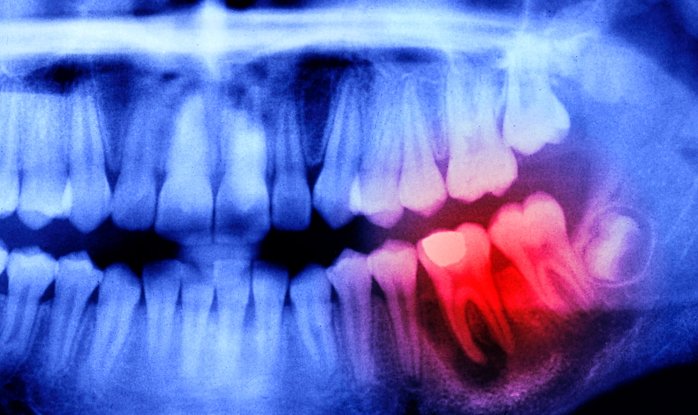

Недавнее исследование группы японских ученых еще раз доказало, что наш организм — это единое целое, и малейшая «неисправность» хотя бы одного из органов незамедлительно отражается на другом. В частности, они выяснили, что проблемы во рту (пародонтит или потеря зубов) повышают риск инсульта, болезни Альцгеймера и других форм слабоумия. В марте к аналогичным выводам пришли их американские коллеги в ходе исследования с участием более 40 тыс. взрослых добровольцев.

По мнению руководителя группы японских ученых Сатоши Ямагучи, здоровая полость рта благотворно влияет на здоровье мозга. И наоборот, по оценке ВОЗ, тяжелыми формами заболеваний пародонта (ткани, окружающие зубы и удерживающие их в альвеоле) страдают почти 20 % взрослого населения (или 1 млрд. человек), что в конечном итоге может отразиться на раннем снижении их когнитивных способностей.